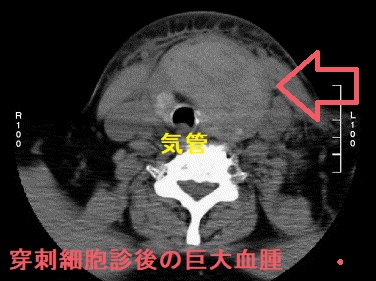

甲状腺穿刺細胞診後の巨大血腫・活動性出血

(報告例)甲状腺穿刺細胞診から3時間後、重度の呼吸困難をきたし、気管内挿管。造影CTで気管を圧排する巨大血腫(上の写真左)と、活動性出血を示唆する造影剤の漏れ(Extravasation)(上の写真右)を確認。

右鎖骨下血管造影にて下甲状腺動脈(ITA)からの活動性出血を同定し、n-ブチルシアノアクリレート(NBCA)を用いた経カテーテル動脈塞栓術(TAE)で止血したそうです(下の写真)

(BMC Surg. 2021 Apr 27;21(1):220.)。